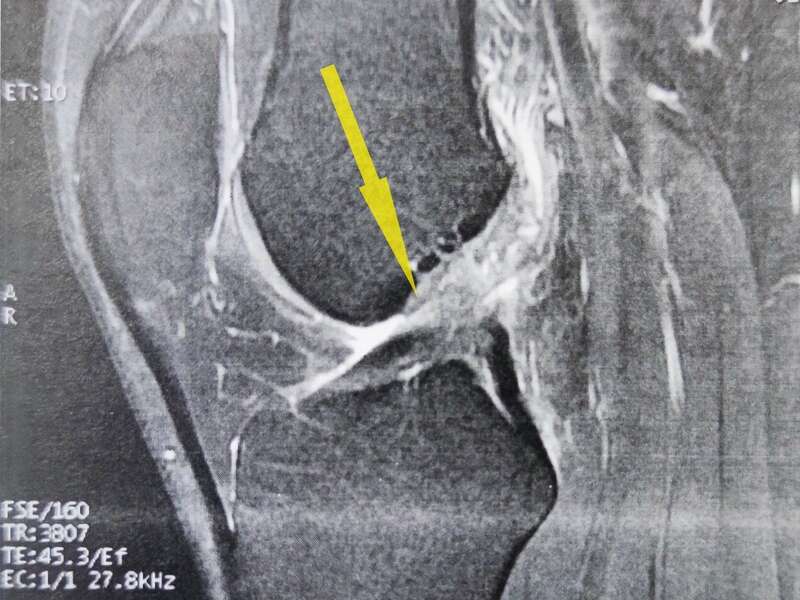

Les lésions des ligaments croisés sont des motifs fréquents de consultation en chirurgie orthopédique. L’examen clinique est primordial pour en faire le diagnostic mais il est indispensable de confirmer ces lésions par une IRM, ou un Arthroscanner.

L’IRM (ou l’arthroscanner) confirmera l’existence d’une rupture ligamentaire et d’éventuelles lésions associées.